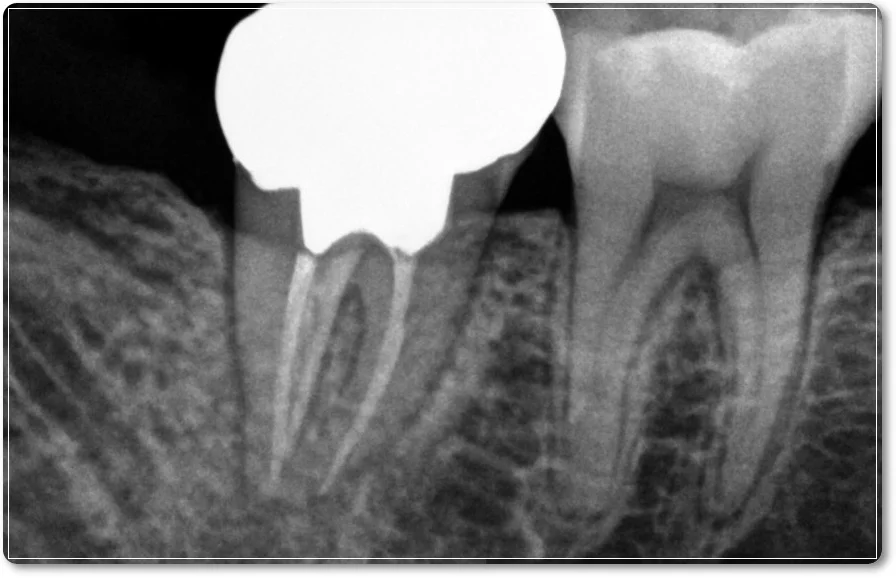

오산 재신경치료 이미 치료한 치아의 통증, 기둥이 세워진 경우 안녕하세요. 서울버팀치과 엄용국 원장입니다. 오늘은 한 환자분의 사례를 소개해 보려고 합니다. 신경치료를 받았던 치아에 다시 증상이 나타나 내원하신 경우였는데요. 신경치료가 끝난...

오산 재신경치료, 다른 치과에서 받았는데 계속 아프다면 안녕하세요. 오산 서울버팀치과 엄용국 원장입니다. “타 치과에서 신경치료를 받고 있습니다. 5~6번 정도 치료를 받았는데 아직도 가만히 있어도 아프고 불편합니다. 다른 치과에서 다시 진료를...